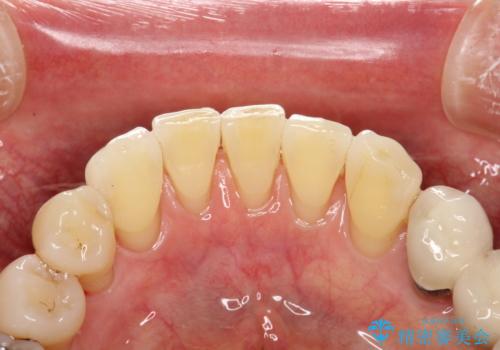

専門的な機械や材料を使用し、60分コースのPMTCクリーニングで、全体的な歯石や着色の除去を行いました。

PMTCは、毎日のブラッシングや食事によって傷ついた歯をツルツルでなめらかにします。継続して定期的に行うことで徐々に歯の表面の凸凹がツルツルになります。日常の飲食や、生活習慣スタイルにより、着色のつき具合には個人差があります。つきやすい方は月に1回のペースからPMTCを行い、徐々につきにくいお口の環境になってきたら3か月に1回のペースでPMTCを行うことがおすすめです。